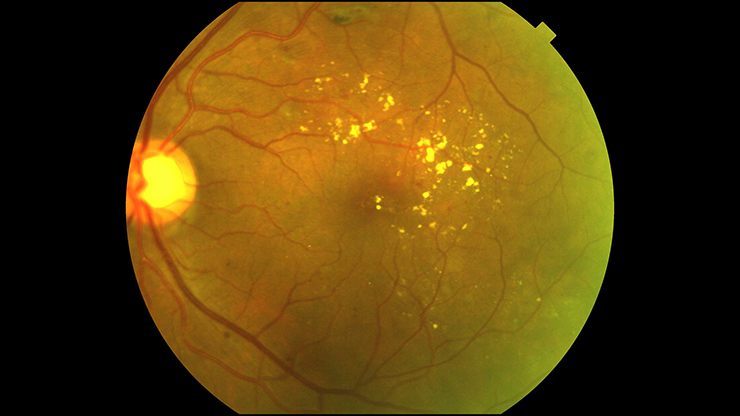

The best way to prevent DME is through regular eye exams, but an estimated 60 percent of people with diabetes don’t obtain these. The exams use a technique called colour fundus photography (CFP), which takes a two-dimensional image of the retina.

Although CFP provides valuable information, the gold standard for diagnosing DME and determining the need for treatment is optical coherence tomography (OCT), which takes a three-dimensional measurement of the macula, the middle part of the retina that increases in thickness with the progression of DME. However, OCT is often unavailable in screening programmes due to cost and technical limitations. A thickness of 250 microns is considered the threshold for the condition, whereas 400 microns is the point at which many ophthalmologists recommend starting treatment.

Our team decided to explore whether we could use deep learning to teach computers how to estimate macular thickness from CFP images, making DME diagnosis easier for patients and ophthalmologists. Currently, CFP images are interpreted by specialists who develop the ability over years to gauge the retina’s thickness from the features they see on its surface, but still need to rely on OCT for confirmation and measurement. Our team wanted to generate similar ability in an automated system.

The deep learning system examined a total of 17,997 CFP images from ~700 patients and compared them with corresponding OCT thickness measurements. The best model we developed using this training set was able to predict macular thickness greater than the 250 micron threshold with an accuracy of 97 percent — an impressive level of performance. Deep learning could even do a reliable job of predicting the actual OCT measurement of the macula’s thickness from a CFP image if it was of sufficient quality.

This initial finding surpassed our expectations, and we wanted to learn more about how it happened. When we looked into it, we were thrilled to find that the computer was focusing on the same parts of the images as specialists have been doing for years, such as the contours and calibre of blood vessels.